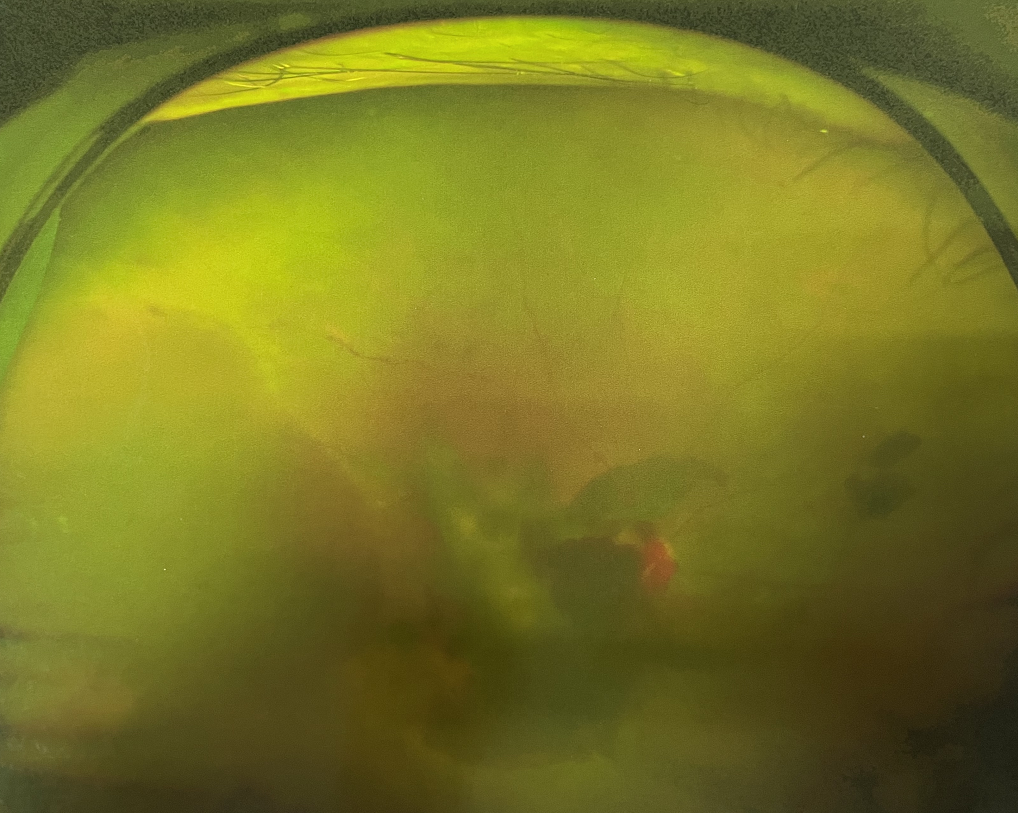

右眼術(shù)前

張小虎醫(yī)生為王女士進(jìn)行右眼玻璃體腔注藥術(shù),3天后進(jìn)行右眼23G玻璃體切割術(shù)后視力有所提升。

4個(gè)月后王女士來院取硅油,取油后視力恢復(fù)到0.6。“當(dāng)時(shí)來的時(shí)候真的只能看到模糊的影子,特別害怕覺得完了,想說眼睛估計(jì)要瞎了,沒想到手術(shù)后視力竟然提升了,現(xiàn)在也看得比較清楚了。”王女士說到。

張小虎醫(yī)生表示,糖網(wǎng)病進(jìn)展到嚴(yán)重增殖期帶來的視力損傷往往是極其嚴(yán)重的,目前王女士右眼從術(shù)前0.02恢復(fù)到術(shù)后0.6,已屬十分難得。